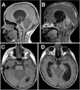

Quadrigeminal body neoplasm